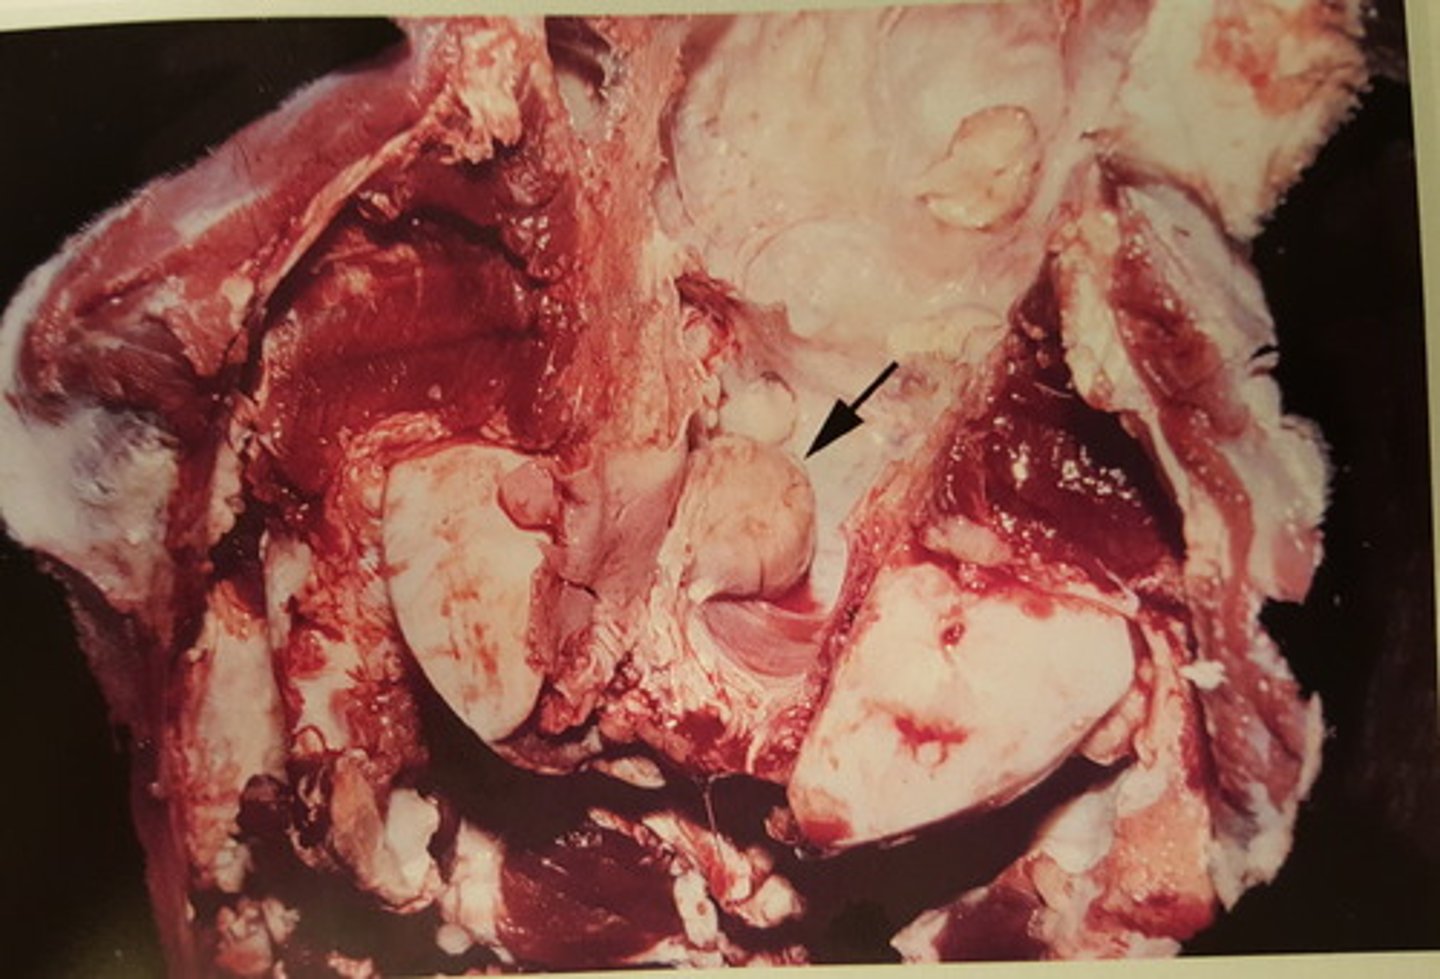

Benign hypofyseneoplasi med hæmorrhagi

Hovede fra hest, hvad er den patoanatomiske diagnose? Se pilen

Benign hypofyseneoplasi

Hypofyse fra hest, hvad er den patoanatomiske diagnose? Se pilen

benign hypofyse neoplasi med hæmorrhagi

Gennemskåret hestehoved. Patoanatomisk diagnose?